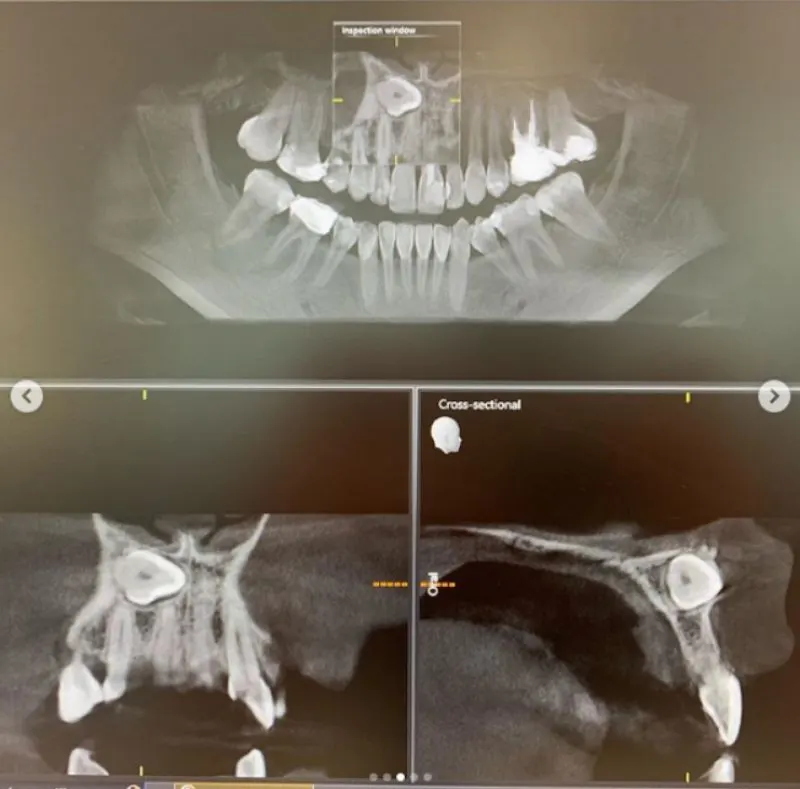

เมื่อวันที่ 2 กรกฎาคม 2562 ไอจีที่ใช้ชื่อว่า b_boomm ได้โพสต์ภาพ นอนที่โรงพยาบาล สาเหตุฟังแล้วก็น่ากลัว สำหรับ บูม สุภาพร ดาราสาว และ พิธีกรดัง หลังพบว่ามีฟันคุด โผล่ตรงด้านหน้า ใกล้เส้นประสาท ตรงกลางหน้า เสี่ยงอันตราย จนต้องเข้ารับการผ่าตัด โดยมีทีมแพทย์ 2 และพยาบาลอีก 5-6 คน พร้อมข้อความระบุว่า...

เย้ ผ่าตัดเสร็จแล้ว ตื่นจากยาสลบเรียบร้อย ขอบคุณ @bdmswellness ที่ดูแลอย่างดี เคสบูม คือมีฟันคุดทางด้านหน้าใกล้เส้นประสาทตรงกลางหน้าเก็บไว้จะเป็นอันตรายอยู่ อาจจะเป็นถุงน้ำ หรือเนืองอกได้อีกด้วย และคลีนิคทั่วไปไม่สามารถผ่าออกได้ ทางคุณหมอดูแลอย่างดี วางยาสลบ ตื่นมาอีกทีก็ฟันไม่มีแล้วค่า เย้ ผ่าฟันที หมอสอง พยาบาลอีก5-6คน ไม่ธรรมดาจริงๆ ฮ่าๆ